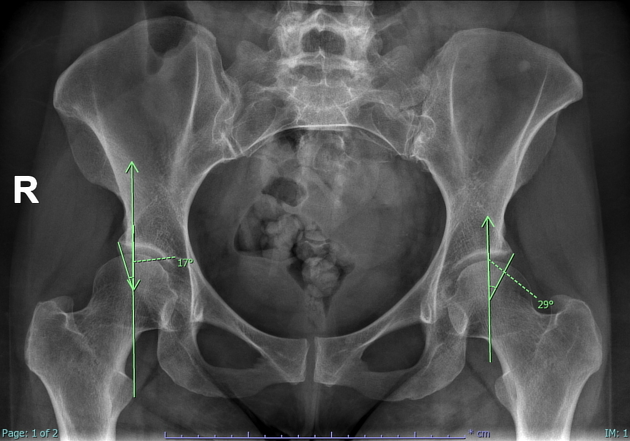

X-ray에서는 대퇴골두(femoral head)와 골반 소켓(acetabulum) 사이의 위치관계를 보게 되는데 pincer type에서는 femoral head와 acetabulum 사이 각도를 봄으로써 충돌 유무를 정량적으로 평가해 볼 수 있습니다.

위의 그림처럼 Pelvis AP view에서 확인할 수 있습니다. Femoral head의 중심에서 수직으로 선을 하나 긋고, 그 중심에서 Acetabulum rim의 가장 바깥쪽으로도 선을 하나 그어 그 사이 각도를 확인합니다.

25-40° 의 각도가 정상이며 40° 이상에서는 pincer morphology로 진단합니다.